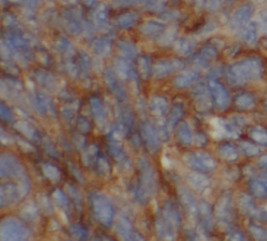

| 验证图片 | Immunohistochemistry of paraffin-embedded human liver cancer using FNab06420(PIK3CB Antibody) at dilution of 1:200 heat mediated antigen retrieved with Tris-EDTA buffer(pH9). Immunofluorescent analysis of ( 10% Formaldehyde ) fixed HeLa cells using FNab06420(PIK3CB antibody) at dilution of 1:50 and Alexa Fluor 488-conjugated Goat Anti-Rabbit IgG(H+L) HepG2 cells were subjected to SDS PAGE followed by western blot with FNab06420(PIK3CB antibody) at dilution of 1:500 |